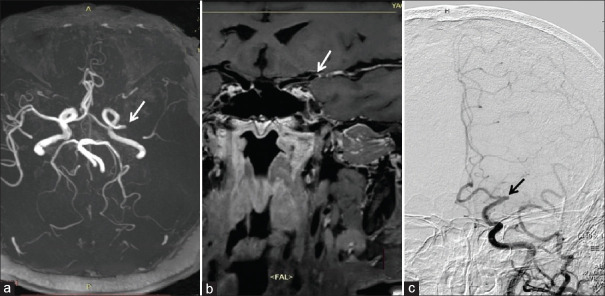

Background and purpose: Detecting the proximal occlusion site (POS) and distal boundary of the occlusion (DBO) of arterial occlusion is very important for the prognosis of endovascular treatment. Recent studies have shown that magnetic resonance imaging (MRI) and magnetic resonance angiography (MRA) are also beneficial for preoperative patient selection for endovascular therapy. High-resolution vessel wall MRI (HRVW-MRI) for intraluminal detection of arterial largevessel occlusions (LVOs) is receiving increasing attention. The purpose of this study was to evaluate the diagnostic efficacy of HRVW-MRI for POS and DBO.

Materials and methods: The data of 42 patients with acute anterior circulation cerebral infarction were retrospectively analyzed. By comparing with digital subtraction angiography (DSA), the POS and DBO were analyzed to determine the efficacy of HRVW-MRI for LVO location.

Results: Good to excellent interobserver consistency was achieved in the analysis and evaluation of all image data (k > 0.70). There was better concordance for the POS between HRMRI and DSA than that between MRA and DSA (k = 0.834 vs. k = 0.309). Compared with DSA, HRVW-MRI showed an advantage over DSA in terms of clearly determining DBO (χ² = 9.389, P < 0.01).

Conclusion: HRVW-MRI demonstrated a comparative advantage over Time-of-flight-MRA for differentiating the POS, with accuracy near-equivalent to that of DSA and a clear advantage over DSA for DBO detection. HRVW-MRI has the potential to improve preoperative planning for endovascular therapy.